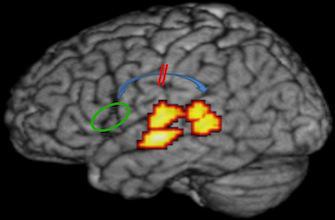

« Coupler l’imagerie et le décodage du signal cérébral, c’est comme si vous aviez enfin la possibilité de savoir du même coup si vos enfants sont rentrés à la maison et s’ils font bien leurs devoirs. Nous avons pu observer que les mêmes zones du cerveau s’activaient dans les 2 populations et qu’elles avaient la même activité », explique Hans Op de Beeck, co-auteur de l’étude. Le dysfonctionnement du cerveau dyslexique n’est donc pas dans la représentation du son mais dans l’utilisation qu’il en fait. L’équipe de Louvain a démontré que si les représentations phonologiques créées dans le cerveau des dyslexiques sont les bonnes, la connexion ne se fait pas correctement entre la zone où elles sont stockées et la région où elles doivent être mobilisées quand la personne lit ou écoute et qu’elle a besoin de faire correspondre les sons et les lettres.